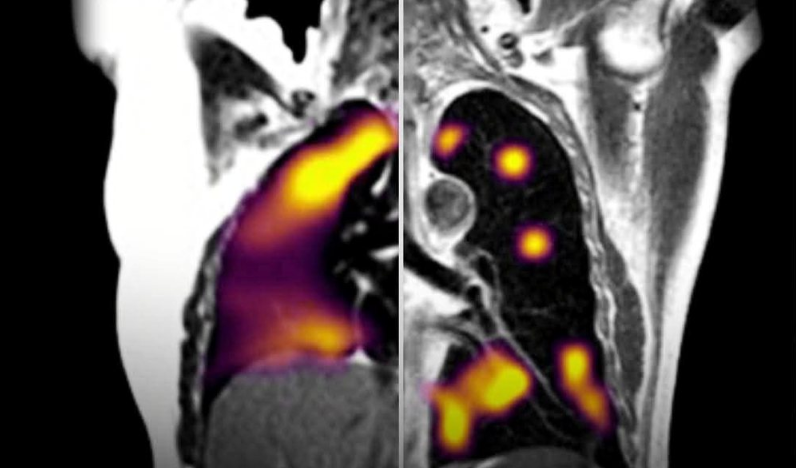

Nga Gazeta Si- Një pacient me HIV, 41-vjeçar është rasti klinik i vetëm deri tani, që përfaqëson infeksionin më të gjatë SARS-CoV-2 të dokumentuar ndonjëherë.

Pacienti me HIV-1 në fazë të avancuar u shtrua 5 herë në spital. Mjekët thotë se nuk mund të flasim për Long Covid, sepse virusi nuk është eliminuar dhe faza e riprodhimit të Covid ka zgjatur më shumë se 750 ditë.

Mostrat virale të pacientit, të mbledhura midis marsit 2021 dhe korrikut 2022, iu nënshtruan analizës gjenetike nga bioinformatiku Joseline Velasquez-Reyes i Universitetit të Bostonit. Analiza fotografoi aktivitetet e virusit me kalimin e kohës, duke regjistruar një shkallë mutacioni të ngjashme me atë që mund të kishte brenda një komuniteti.

Disa variacione janë gjetur në proteinën Spike, atë që virusi përdor për të infektuar qelizat e synuara. Dhjetë nga këto variacione korrespondonin me të njëjtat pozicione të vërejtura në variantin Omicron.

Prandaj, të njëjtat lloje mutacionesh që çuan në shfaqjen e një varianti të ri mund të ndodhin brenda një personi të vetëm.

Sipas studiuesve, kjo mbështet teorinë se ndryshimet janë zhvilluar për shkak të presioneve selektive që pëson virusi brenda trupit tonë.